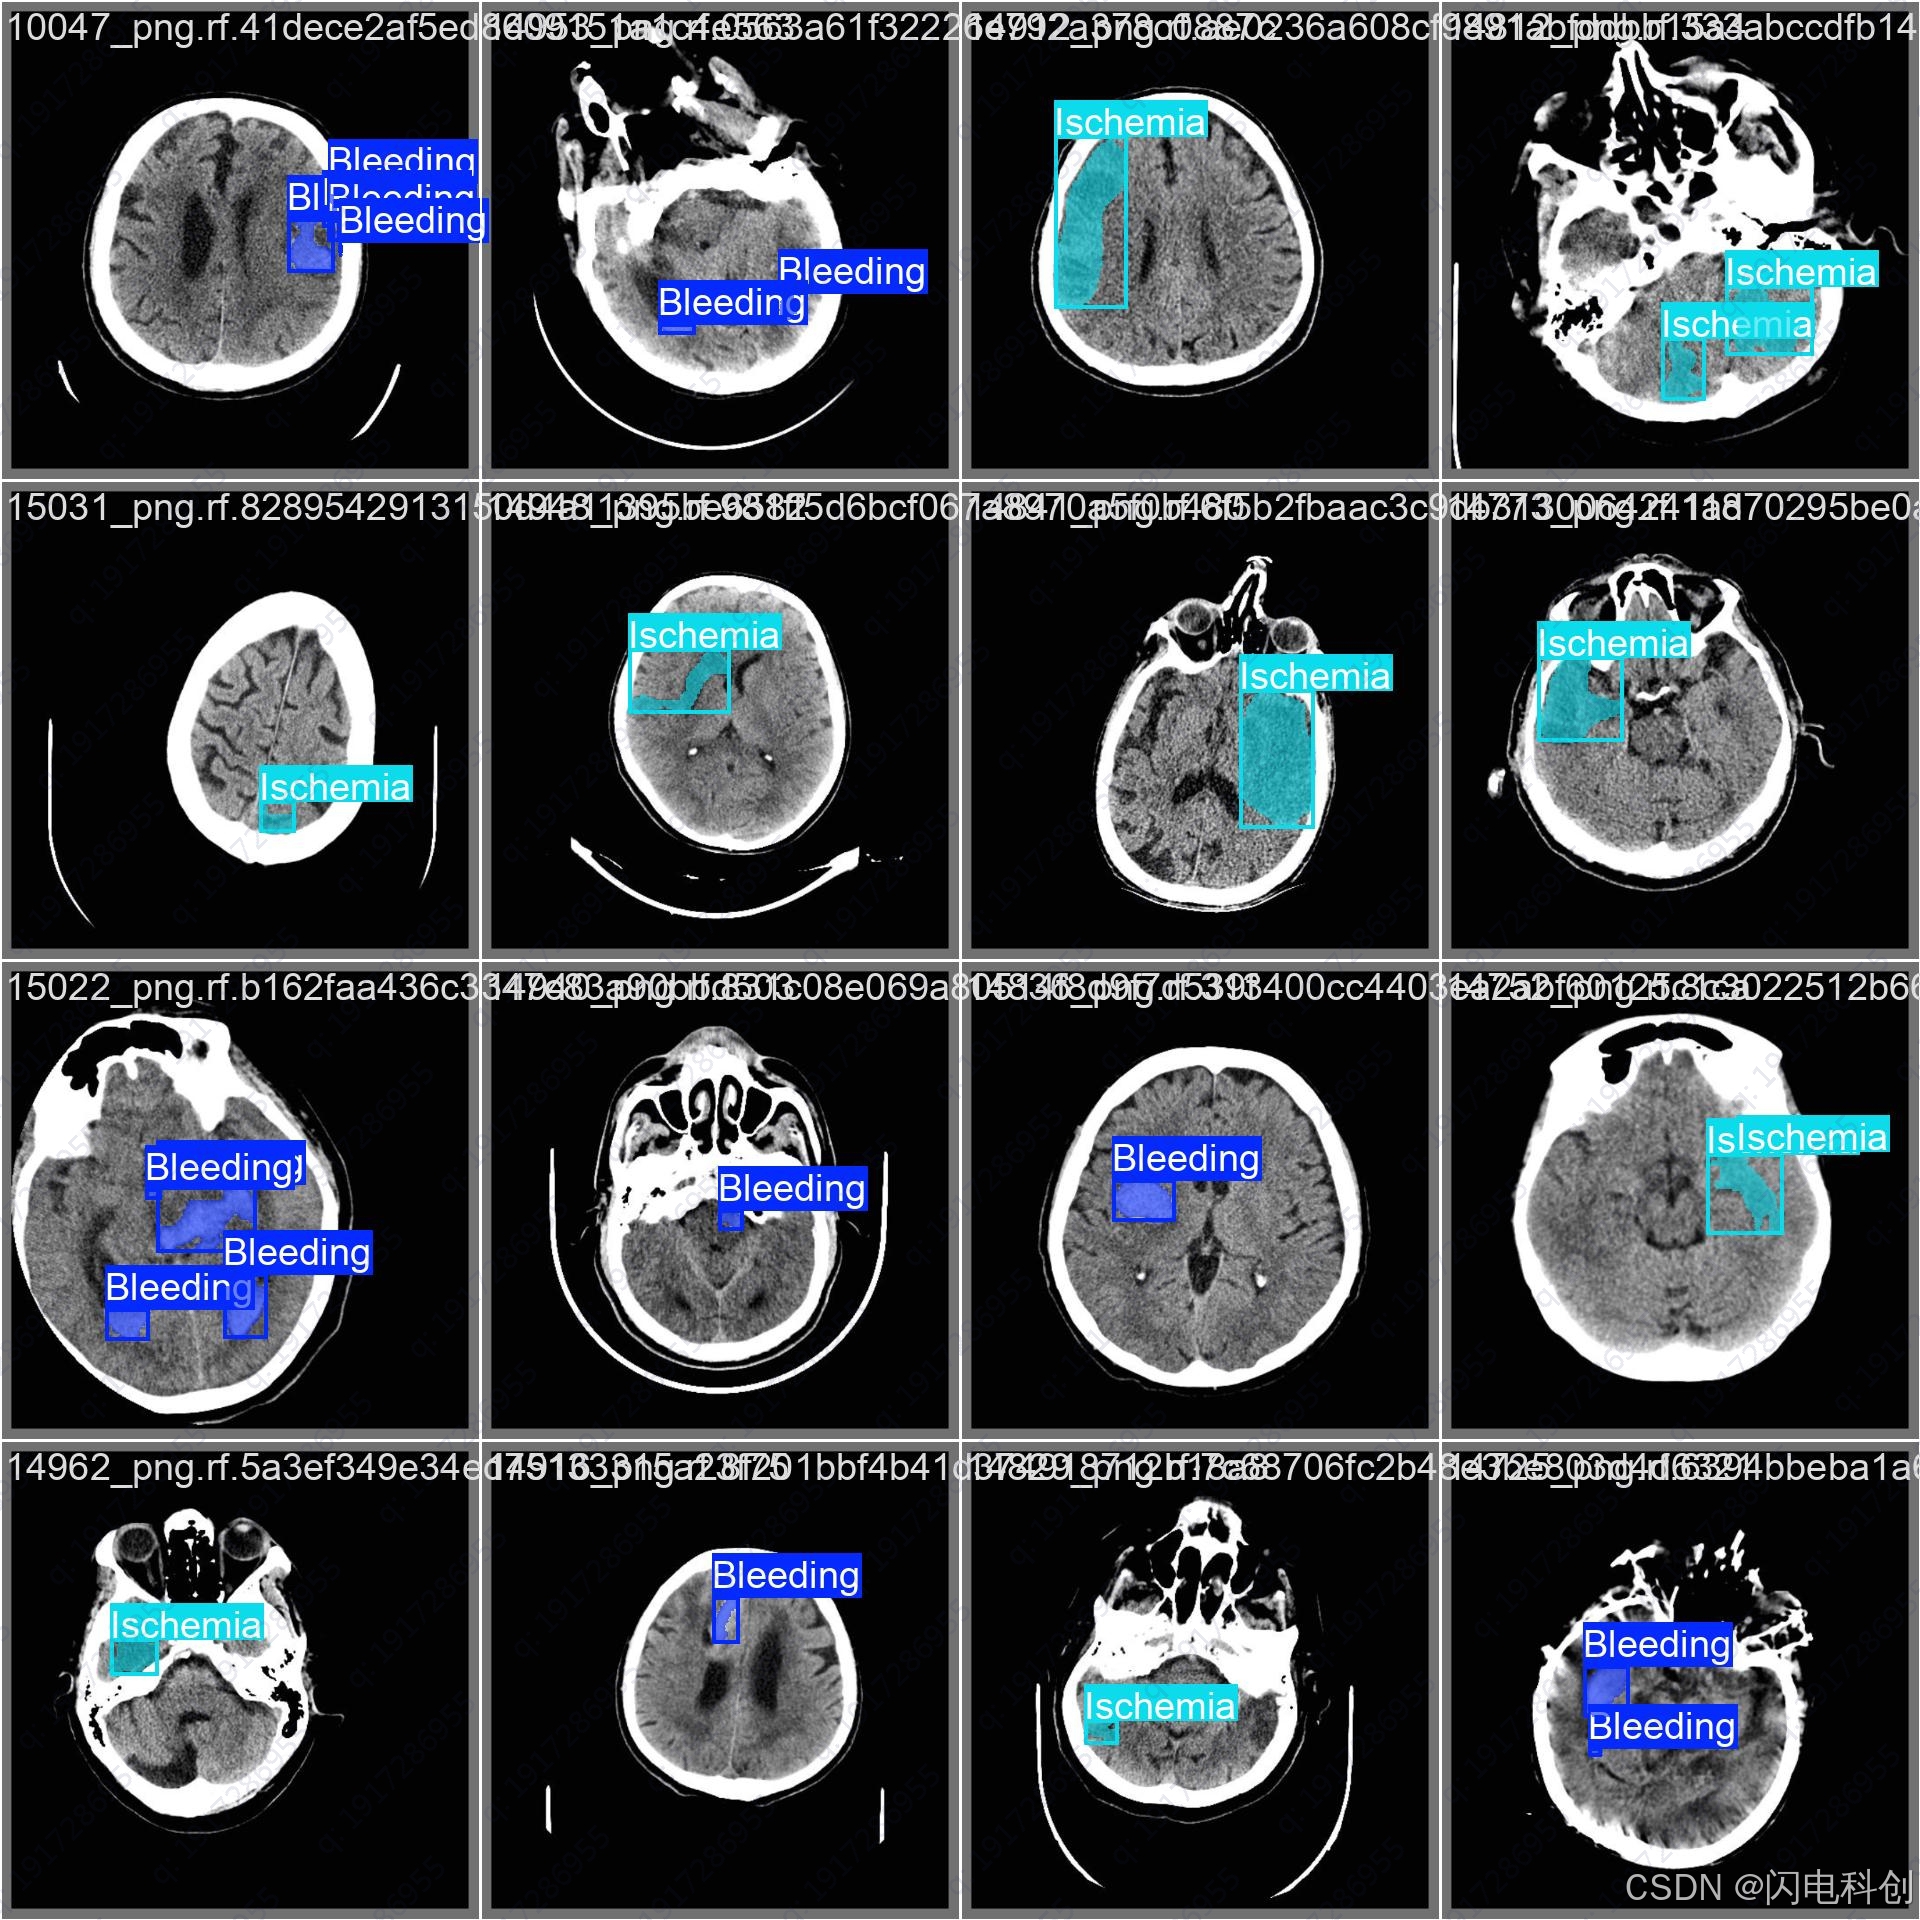

脑卒中实例分割(Stroke Instance Segmentation)是当前医学影像分析领域的研究热点之一。其研究目标是精确定位并分割出脑卒中病灶的不同区域(例如:核心区、半暗带、出血区域等),并识别每一个独立病灶实例(instance)。近年来,随着深度学习、图神经网络、跨模态建模等技术的发展,脑卒中实例分割在方法论和应用层面都出现了许多创新点。

以下是脑卒中实例分割中的若干前沿创新方向,涵盖模型结构设计、数据利用方式、标注优化、解释性增强等维度: